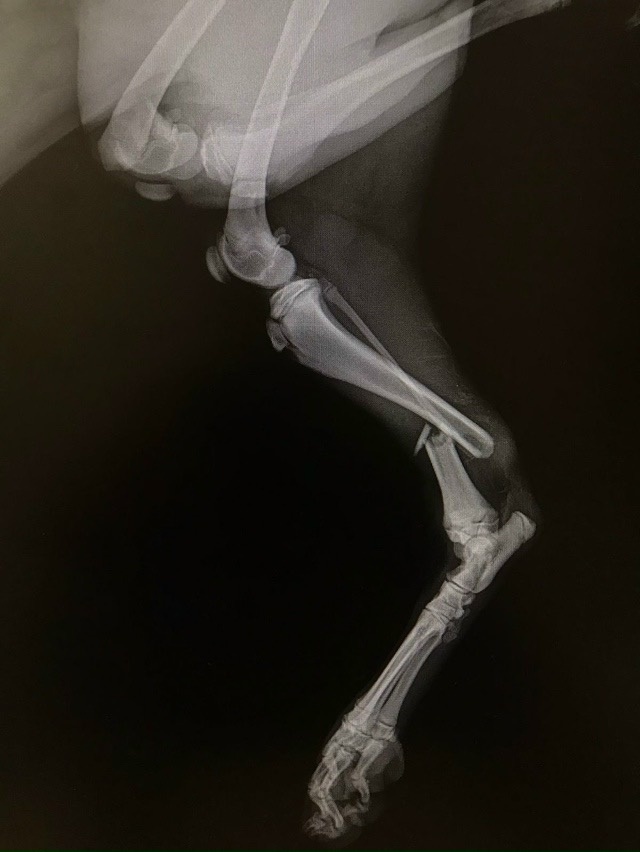

Вечером воскресенья наш маленький мир перевернулся, когда мы узнали, что бездомный щенок, девочка, попала под машину на Объездной дороге. Она была совершенно одна, и только удача привела её в клинику, где ей дали имя Кукла. После ужасного инцидента ей диагностировали перелом двух лап. Это требовало срочной и сложной операции.

Операция оказалась сложной: для сращивания костей были использованы специальные пластины и другие медицинские средства. Но Кукла не сдавалась! Она мужественно переносила все процедуры и, несмотря на трудности, проявляла невероятное терпение.